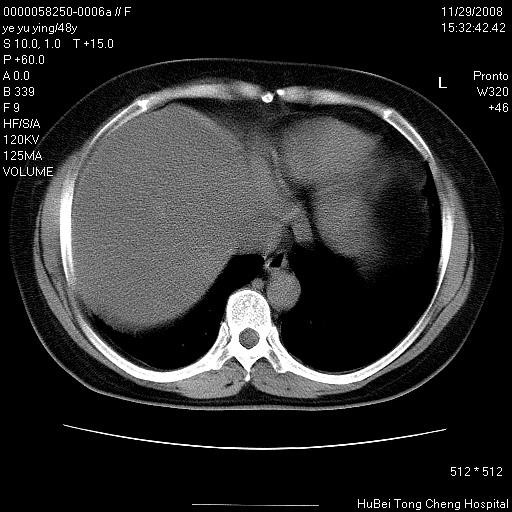

以下是引用zsl6918在2008-11-29 21:47:00的发言:[br]恶性肿瘤病史,转移瘤首先考虑。脂肪肝,胆囊结石。

以下是引用huenhao在2008-11-29 22:11:00的发言:[br]脂肪肝,胆囊结石。左肺病灶建议定期复查。

以下是引用liuyue在2008-11-30 5:44:00的发言:[br]1.左肺病变,首先考虑感染性病变,转移待排;建议治疗后复查。[br]2.肝脏密度普遍减低,考虑与化疗有关。[br]3.胆囊结石.